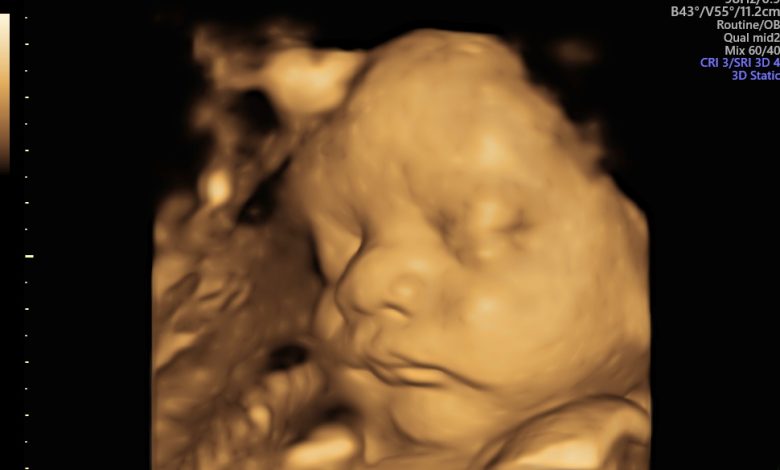

Баланы дамуы: Бұл аптада бала шамамен 1,5–1,7 кг салмақ жинап, бойы 40–42 см-ге жетеді. Өкпесі толық жетілмесе де, тыныс алуға дайындық жүріп жатыр. Нәресте қозғалысы айқын сезіледі, кейде іштің белгілі бір бөлігінде ауырлық немесе тырысу сезімі болуы мүмкін.